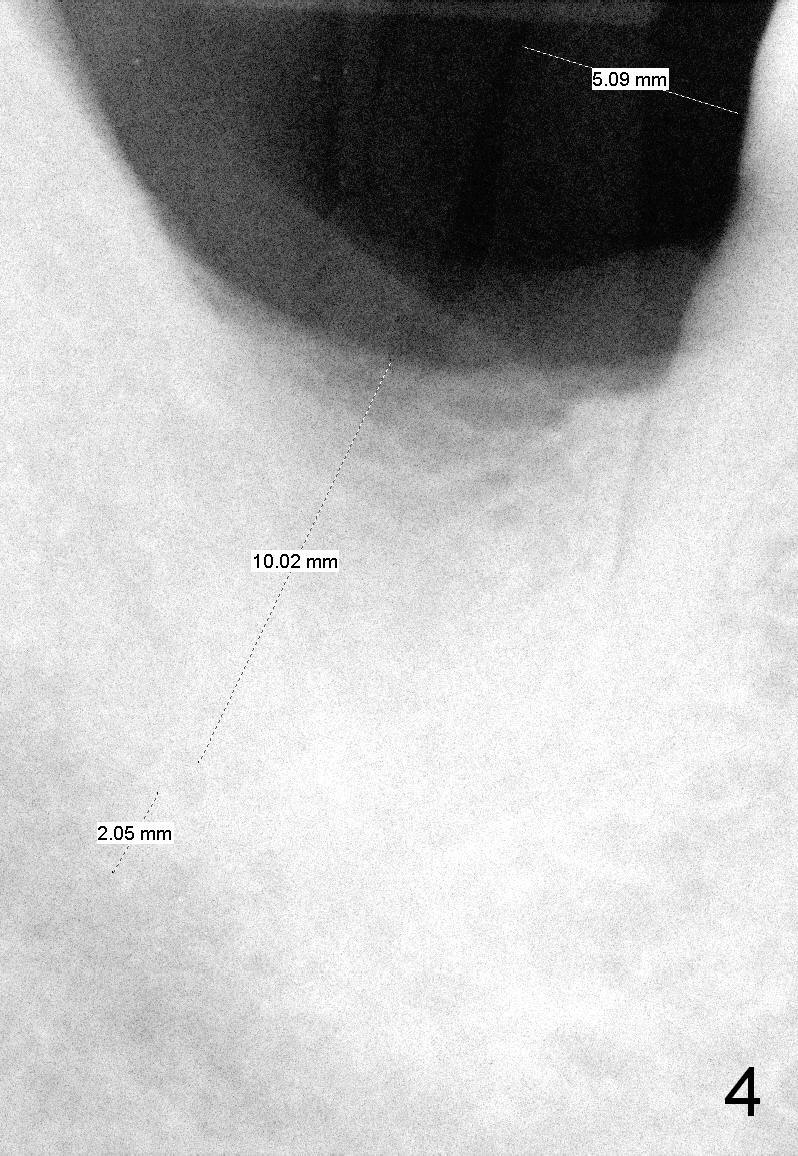

After successful immediate implant at the site of #2, he agrees to have an implant at the site of #31. The bone height has reduced to 13 mm; it appears that a 10 mm bone-level implant is appropriate (Fig.4).

When a parallel pin is inserted with the depth of 10 mm, there is 3 mm from the superior border of the Inferior Alveolar Canal (Fig.5).